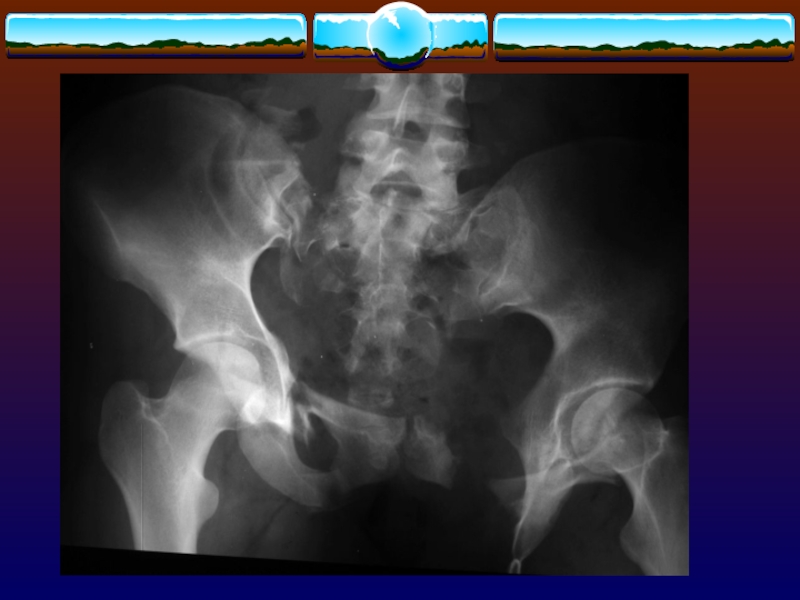

Слайд 67Этиология

ДТП 60 %

падения 30 %

Летальность

общая 15 %

30

% при открытых переломах

45 % у пациентов с гипотензией

при

поступлении

ЭтиологияДТП 60 % падения 30 %Летальность общая 15 % 30 % при открытых переломах 45 % у

Слайд 68Сопутствующие повреждения при тяжелых переломах.

в 50 % случаев повреждения органов

брюшной полости

в 15 % случаев повреждения мочеиспускательного канала

в 10 %

случаев повреждения мочевого пузыря

Сопутствующие повреждения при тяжелых переломах. в 50 % случаев повреждения органов брюшной полостив 15 % случаев повреждения